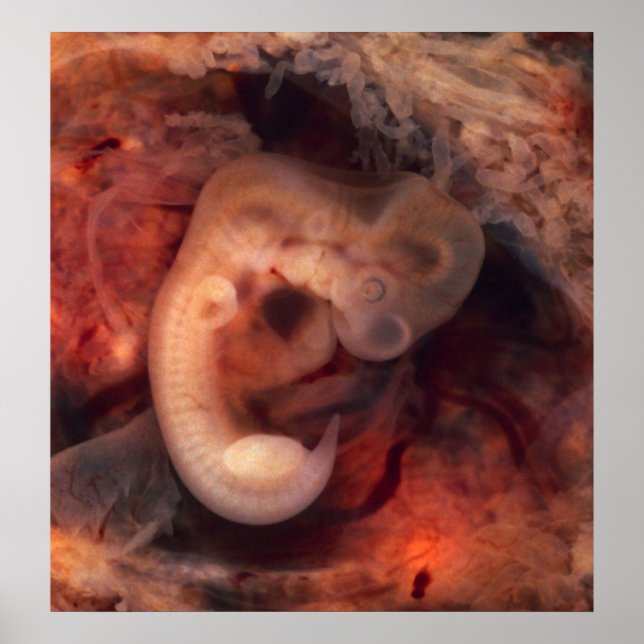

Human Embryo (7th week of pregnancy, 5th week p.o.)

This photo of an opened oviduct with an ectopic pregnancy features a spectacularly well preserved 10-millimeter embryo. It is uncommon to see any embryo at all in an ectopic, and for one to be this well preserved (and undisturbed by the prosector's knife) is quite unusual.

Even an embryo this tiny shows very distinct anatomic features, including tail, limb buds, heart (which actually protrudes from the chest), eye cups, cornea/lens, brain, and prominent segmentation into somites. The gestational sac is surrounded by a myriad of chorionic villi resembling elongated party balloons. This embryo is about five weeks old (or seven weeks in the biologically misleading but eminently practical dating system used in obstetrics).